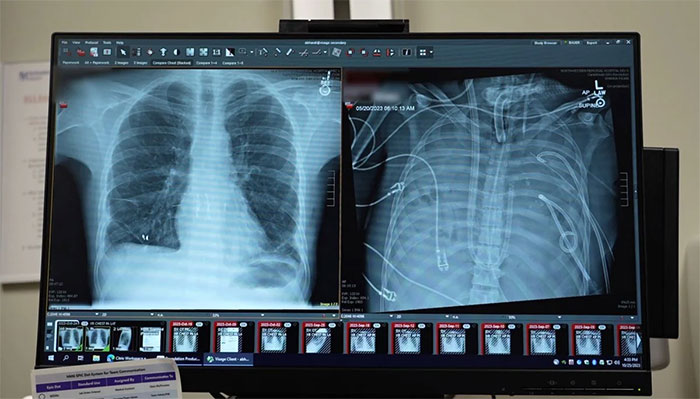

In a study published in the scientific journal Med (published by Cell Press), surgeons described how they completely removed two severely infected lungs from a patient, then sustained him with a custom-designed 'artificial lung' system until a suitable donor lung could be found. The research team suggests this method could become a lifeline for patients at risk of dying while awaiting organ transplantation.

To buy time while waiting for a transplant, the team of doctors developed a temporary system that could perform the vital functions of the lungs. This device delivers oxygen to the blood, removes carbon dioxide, and supports circulation, helping the heart continue to pump blood efficiently even though the body no longer has lungs.

After the two infected lungs were removed, the patient's condition began to improve significantly. Blood pressure stabilized, other organs gradually regained function, and the infection was brought under control. Two days later, the team found a suitable donor lung and successfully performed the double transplant.

In-depth analysis of the removed lungs revealed severe fibrosis and a high degree of immune damage. Molecular tests confirmed that the damage had exceeded the lungs' ability to heal naturally.